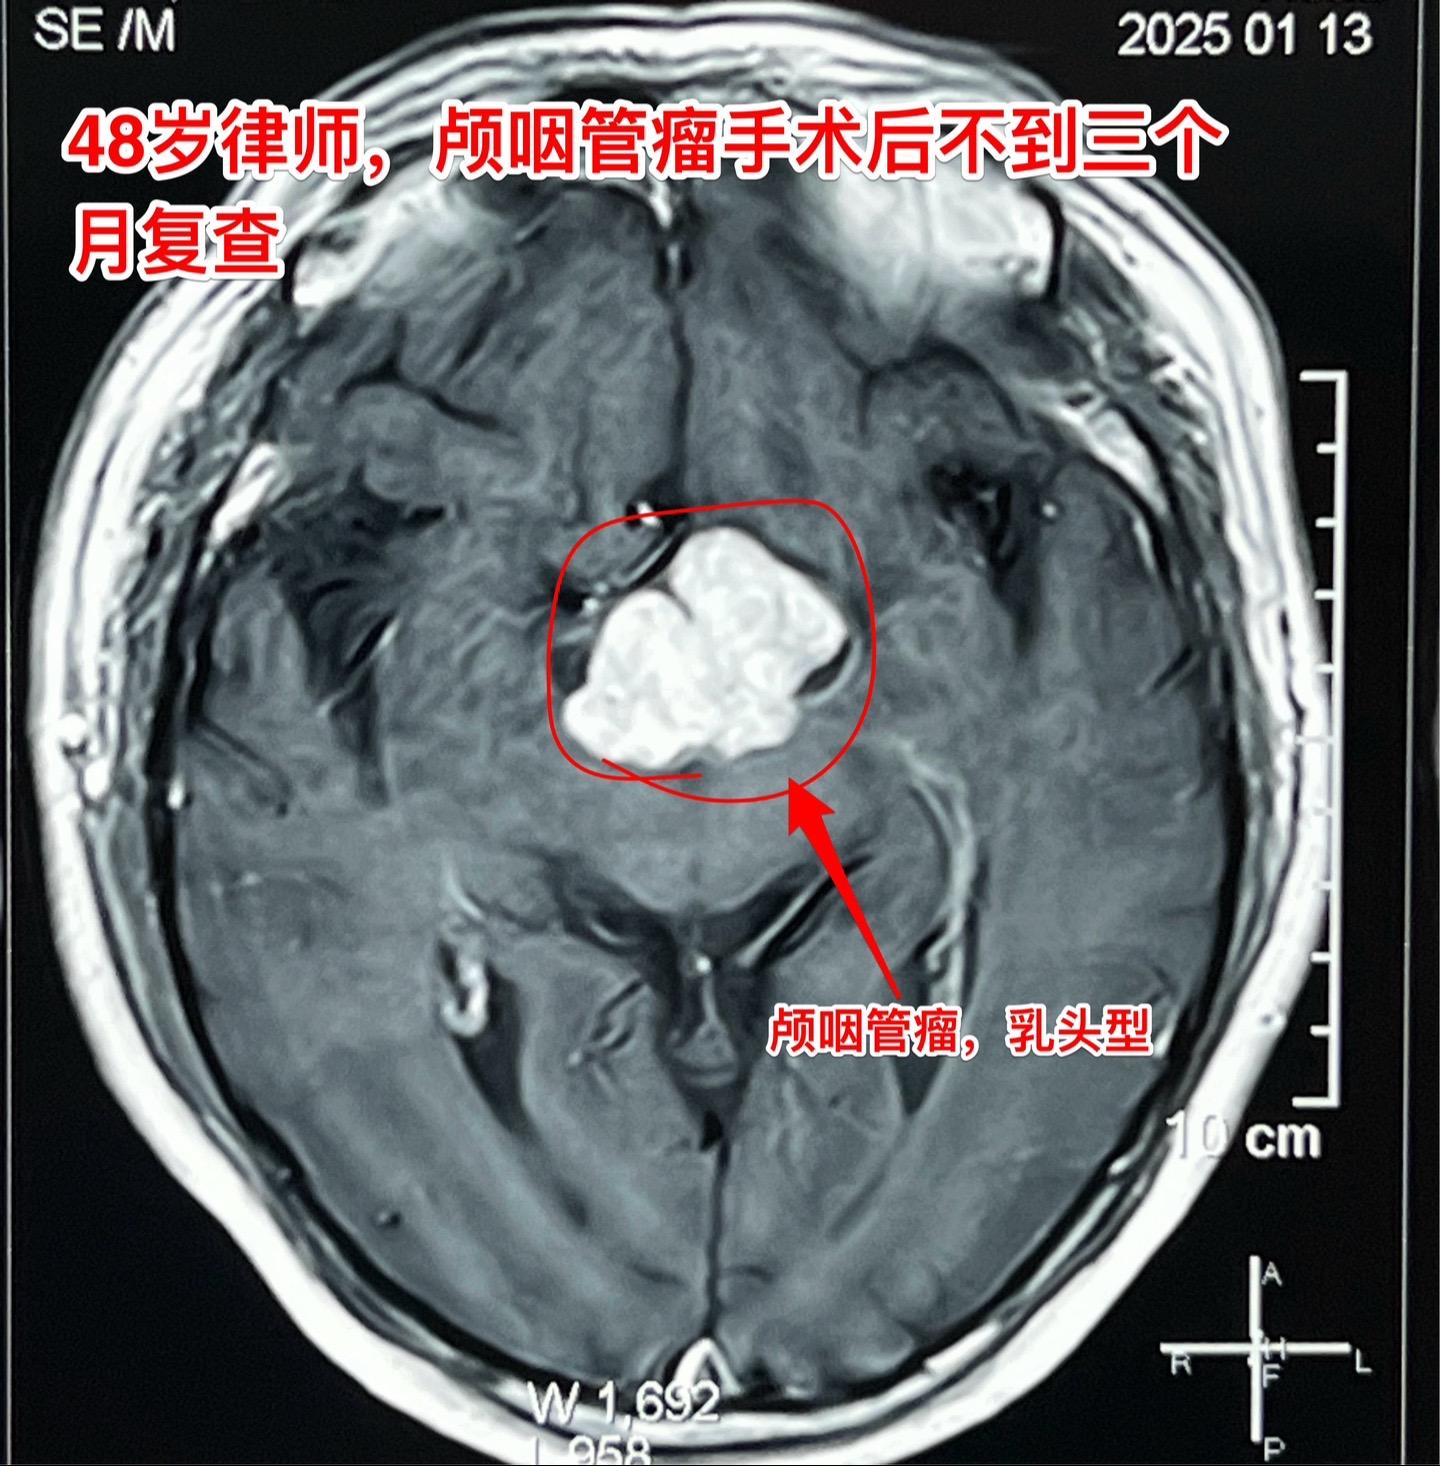

48岁律师,颅咽管瘤术后三个月复查。律师在四川凉山工作,在四川某医院手术未满三个月,自手术后就有记忆力差、爱睡觉等体积症状,难以胜任律师工作。复查磁共振显示颅咽管瘤体积仍然很大,怀疑为肿瘤复发了。 患者家人治病心切,直接到北京找我做手术。 今天是腊月二十四,还有5天就过年了。今天为律师作了开颅手术,将肿瘤完全切除了。希望颅咽管瘤不再复发。